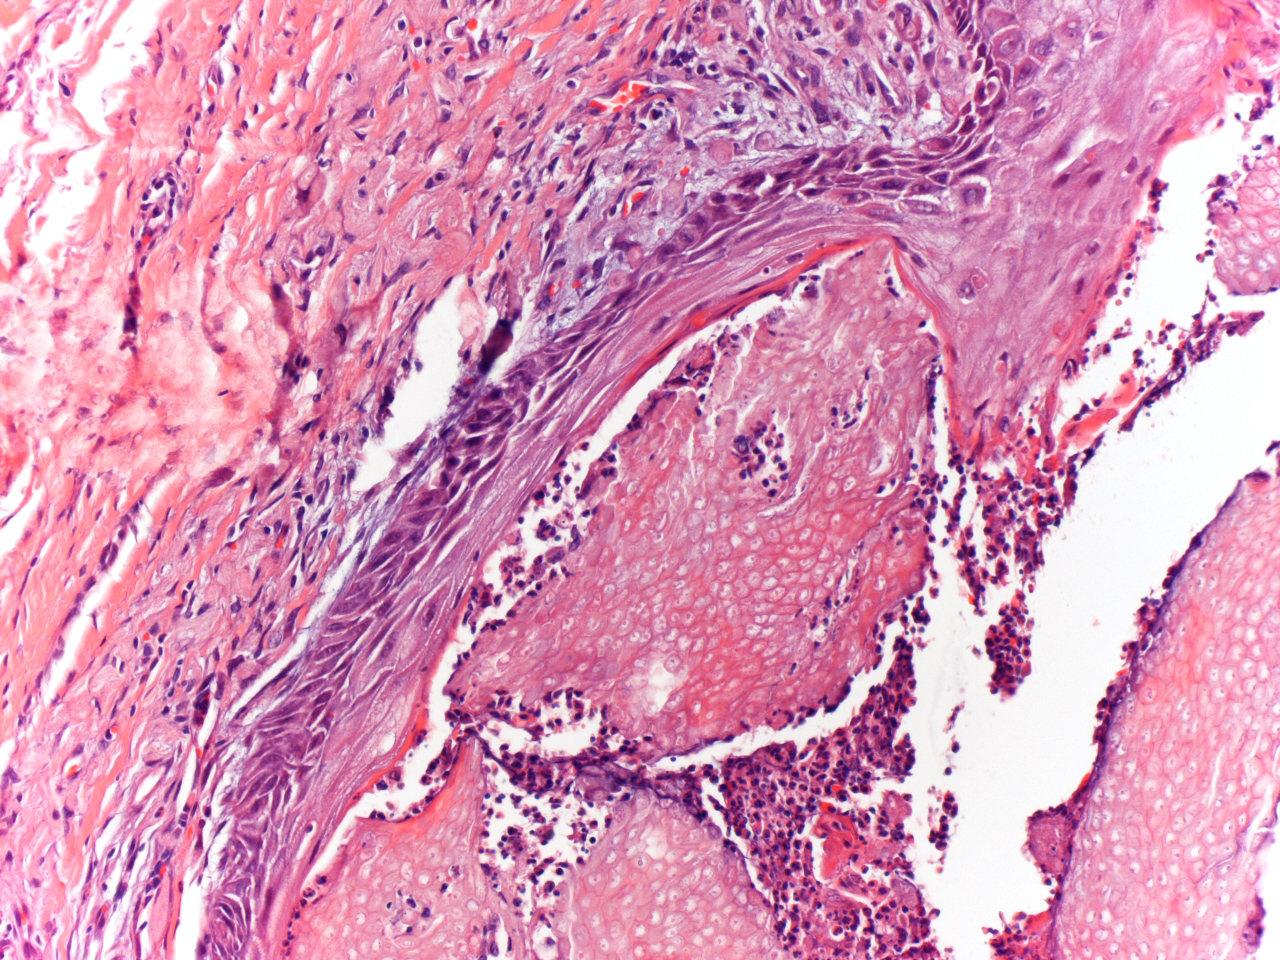

Fig 3: Present islands of eosinophilic shadow cells perforating to epidermis (original magnification, H&E x200).